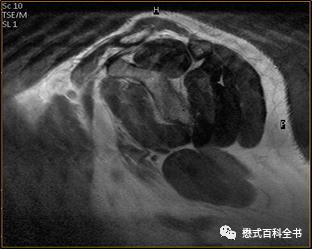

图10、11:打火花伪影表现

Spike伪影的表现还是比较典型的,一般称为电火花伪影。问了一下FSE工程师,这个伪影产生原因是,硬件系统不稳定,在采集信号的时候产生一些打火花,然后在图像上表现就是一条线状影。在整个采集信号的过程中,打了多少火花,可能就产生了多少条这种线状伪影。总结一下就是封闭磁体间内某些放电辐射导致斑马线伪影产生。

伪影表现主要为:覆盖整个图像的斑马线状伪影。可为单一方向,也可为多个方向相交排列。可出现在序列的某一幅图像中,也可出现在整个序列。